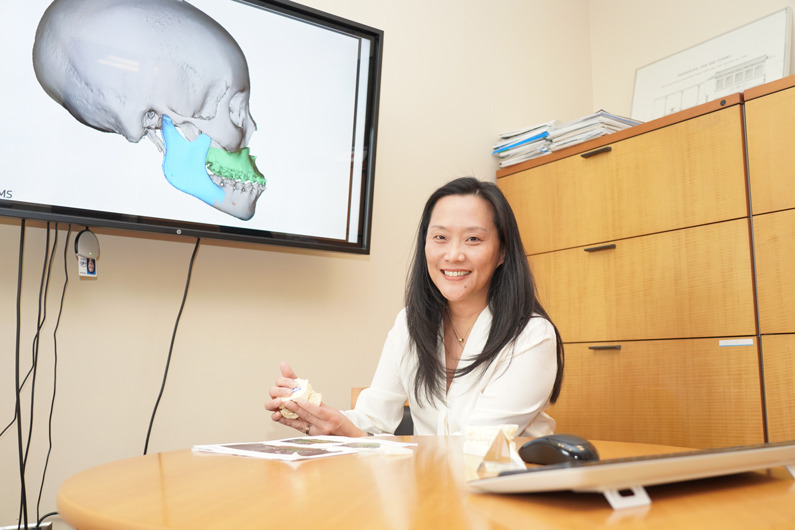

Janice S. Lee, DDS, MD, MS, has been named the 2019 recipient of the William J. Gies Foundation for the Advancement of Dentistry of the American Dental Education Association, Inc. Award in Oral and Maxillofacial Surgery. She is the first woman surgeon to receive this honor. The award, which recognizes distinguished achievement in the field, will be presented in September at the 101st annual meeting of the American Association of Oral and Maxillofacial Surgeons in Boston.

NIDCR’s Clinical Director Conducted First Underbite Surgery at NIH

The spring 2019 Clinical Center News features Janice Lee, who conducted a five-hour operation to successfully fix the underbite of college student Trina Davis. Before surgery, Davis had difficulty eating and speaking. "I had to go to speech therapy to figure out how to form my words correctly. Now, I'm able to better pronounce my words the way I want to,” she says. To prepare, Lee worked for weeks with 3D cone-beam computed tomography, which helped her simulate facial surgery.